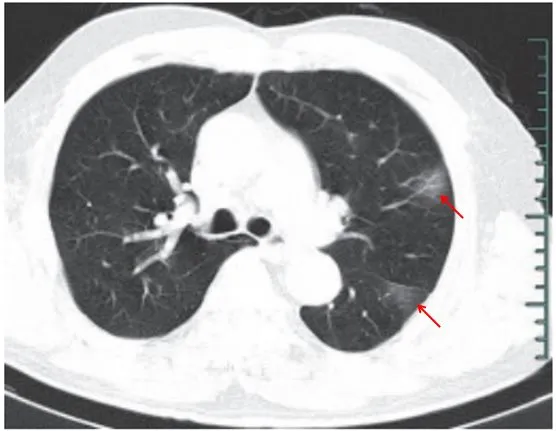

(三)病灶密度

绝大多数案例出现磨玻璃病灶,最低测得 CT 值约为-600Hu(图 2-3) ,病灶内血管穿行可清晰显示;部分案例磨玻璃病灶与实性病灶共存

根据既往严重急性呼吸综合征(SARS)病理学机制,提示此为肺泡间隔毛细血管扩张充血、肺泡腔内液体渗出和小叶间隔间质水肿

图 2-3 早期绝大多数病灶表现为磨玻璃密度(共4张 )